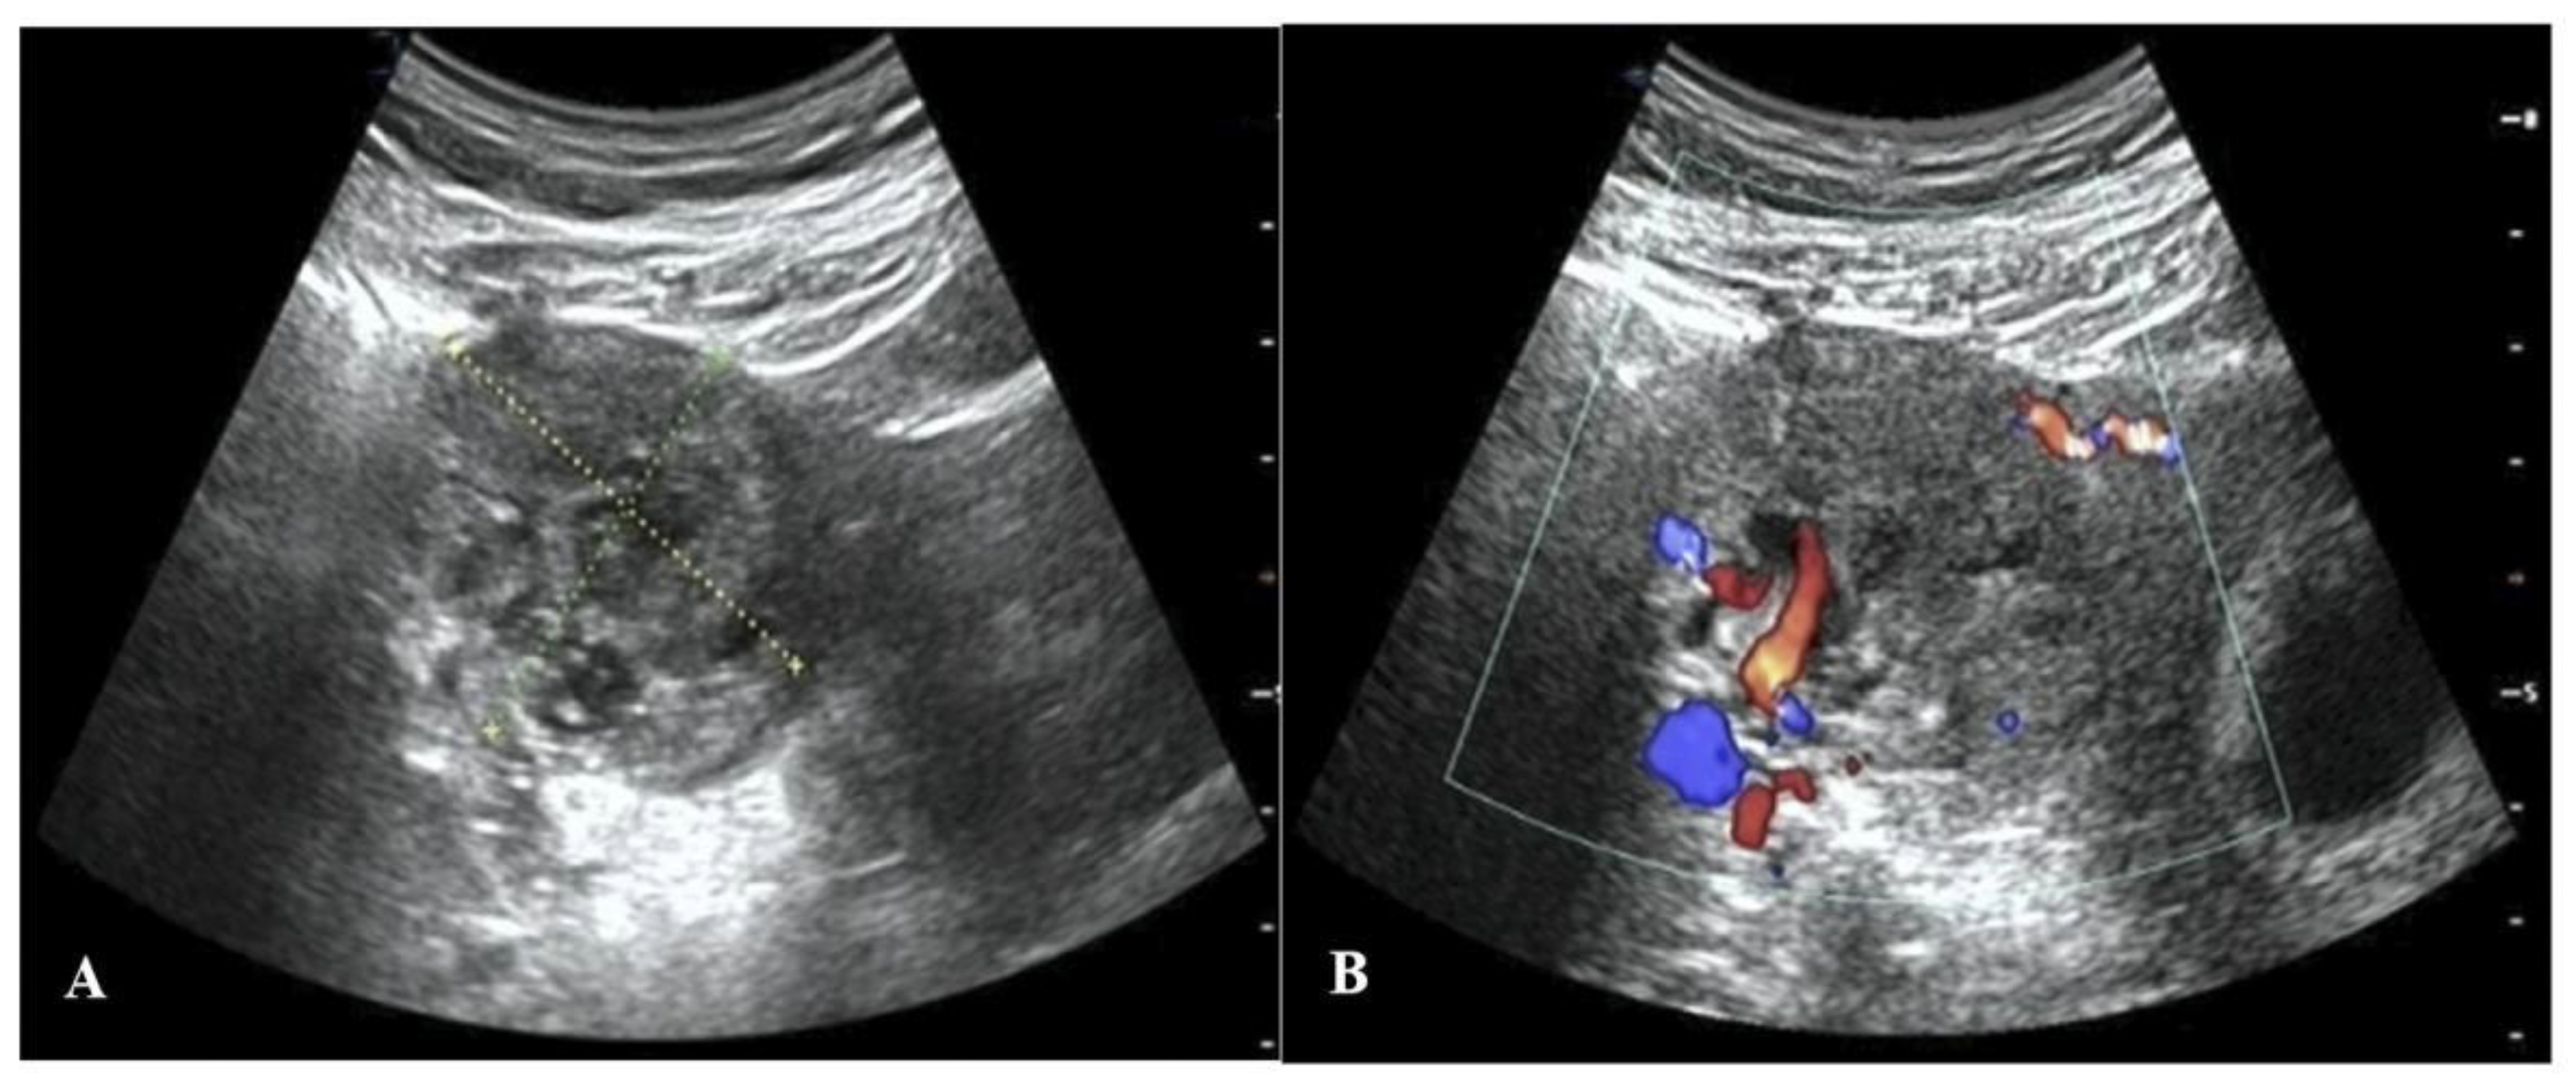

Given that this IP was still growing, it was necessary to promptly inactivate the EP. Two treatment options were presented to the patient: laparoscopic surgery or fetal reduction treatment. Ultimately, the patient and her partner gave written consent for the patient to undergo the ultrasound-guided local injection of methotrexate (MTX) to inactivate the interstitial gestational sac after fully understanding the possible risks to the mother and fetus. For the procedure, the patient lay in the supine position with her lower abdomen fully exposed. The puncture point was chosen, and the drape was then routinely disinfected. Under the real-time guidance of ultrasound, an 18G puncture needle was advanced to the villus implantation site of the right IP, after which 20 mg of MTX (0.4–0.5 mg/kg body weight was dissolved in 5 mL of normal saline) was slowly injected into the interstitial gestational sac [6]. The needle was then pulled out after inserting the needle core. The process went smoothly. Subsequent serial ultrasound scans and serum β-hCG level tests were performed to dynamically observe the changes in the EP and IUP. On the second day after injection, the interstitial gestational sac measured about 32 × 22 mm, and there was a slight streak-like blood flow signal around it. On the 7th day, there was no significant change in the ectopic gestational sac, and the serum β-hCG level was 235,123 IU/L. On the 14th day, the ectopic gestational sac was larger, about 44 × 43 mm in size, with abundant peripheral blood vessels (Figure 2). On the 18th day, the ectopic gestational sac had grown to its largest size, about 58 × 40 mm. After this, it became increasingly smaller until the 22nd week of gestation, when it was about 35 × 30 mm in size and surrounded by fewer blood vessels. On the 20th day, the serum β-hCG level of the patient was 85,702 IU/L. The changes in the size of the interstitial gestational sac and the serum β-hCG level are respectively presented in Figure 3A,B.

Figure 2.

Ultrasound images on the 14th day after the injection of MTX. (A) A two-dimensional ultrasound image, which reveals the growth of the ectopic gestational sac. (B) A color Doppler ultrasound image showing an abundant blood flow signal around the IP.